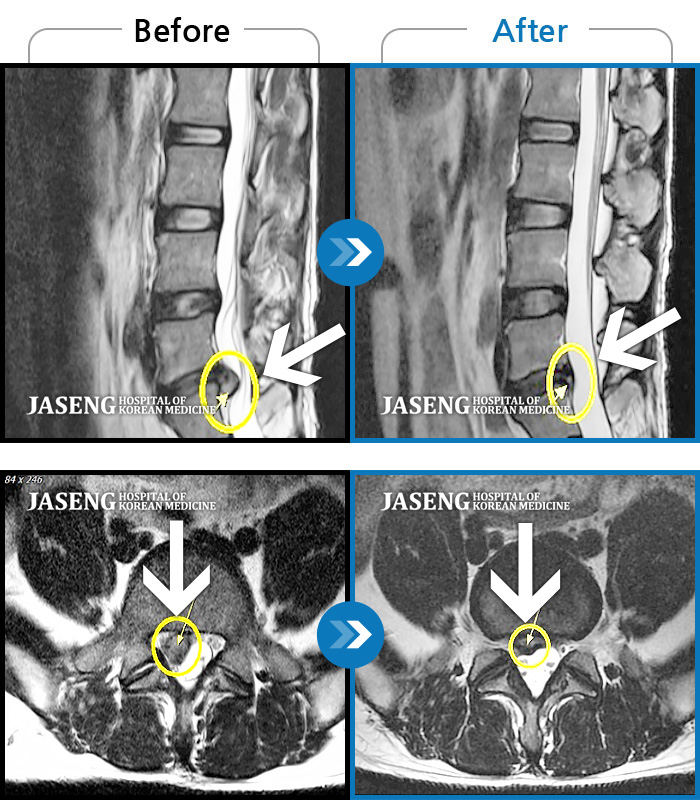

MRI 치료사례

양쪽 허리, 엉치, 골반쪽으로 불편감, 우측 다리 저림